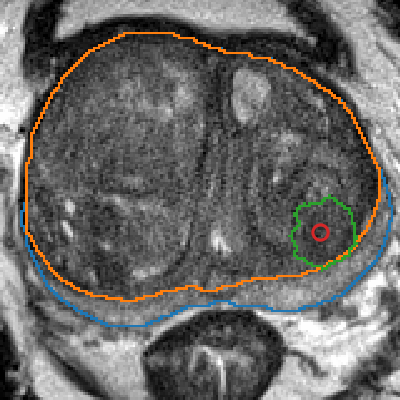

The emergence of multi-parametric magnetic resonance imaging (mpMRI) has had a profound impact on the diagnosis of prostate cancers (PCa), which is the most prevalent malignancy in males in the western world, enabling a better selection of patients for confirmation biopsy. However, analyzing these images is complex even for experts, hence opening an opportunity for computer-aided diagnosis systems to seize. This paper proposes a fully automatic system based on Deep Learning that takes a prostate mpMRI from a PCa-suspect patient and, by leveraging the Retina U-Net detection framework, locates PCa lesions, segments them, and predicts their most likely Gleason grade group (GGG). It uses 490 mpMRIs for training/validation, and 75 patients for testing from two different datasets: ProstateX and IVO (Valencia Oncology Institute Foundation). In the test set, it achieves an excellent lesion-level AUC/sensitivity/specificity for the GGG$\geq$2 significance criterion of 0.96/1.00/0.79 for the ProstateX dataset, and 0.95/1.00/0.80 for the IVO dataset. Evaluated at a patient level, the results are 0.87/1.00/0.375 in ProstateX, and 0.91/1.00/0.762 in IVO. Furthermore, on the online ProstateX grand challenge, the model obtained an AUC of 0.85 (0.87 when trained only on the ProstateX data, tying up with the original winner of the challenge). For expert comparison, IVO radiologist's PI-RADS 4 sensitivity/specificity were 0.88/0.56 at a lesion level, and 0.85/0.58 at a patient level. Additional subsystems for automatic prostate zonal segmentation and mpMRI non-rigid sequence registration were also employed to produce the final fully automated system. The code for the ProstateX-trained system has been made openly available at https://github.com/OscarPellicer/prostate_lesion_detection. We hope that this will represent a landmark for future research to use, compare and improve upon.